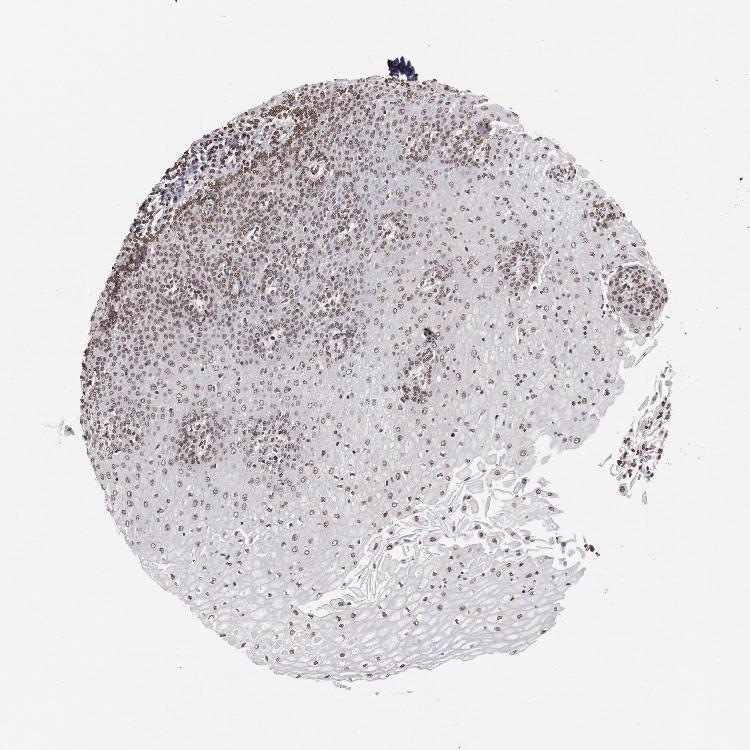

ESOPHAGUS - Antibody stainingi

Antibody staining in the annotated cell types in the current human tissue is reported as not detected, low, medium, or high, based on conventional immunohistochemistry profiling in selected tissues. This score is based on the combination of the staining intensity and fraction of stained cells.

Each image is clickable and will lead to virtual microscopy that enables deeper exploration of all samples and also displays staining intensity scores, fraction scores and subcellular localization as well as patient and tissue information for each sample.

Antibody HPA002891Antibody CAB003765Antibody CAB080436

Squamous epithelial cells MediumMediumMedium